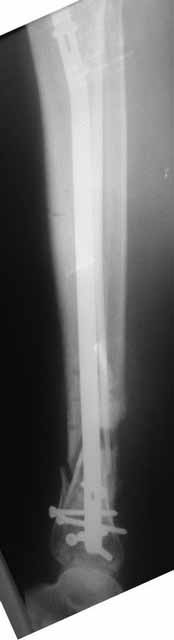

Как-то вот нет уже желания открываться в зоне ложного сустава. Мы бы

попытались сделать закрыто. Винт в дистальном отломке удалить через прокол.

Кусок гвоздя оставить. Новый гвоздь (солидный), возможно с покрытием.

Немного потянули по оси, убрали вальгус, ротацию. 22 апреля (на 3-е сутки) заштифтовали окончательно. 29 апреля выписали из отделения. На все ушло 10 дней.